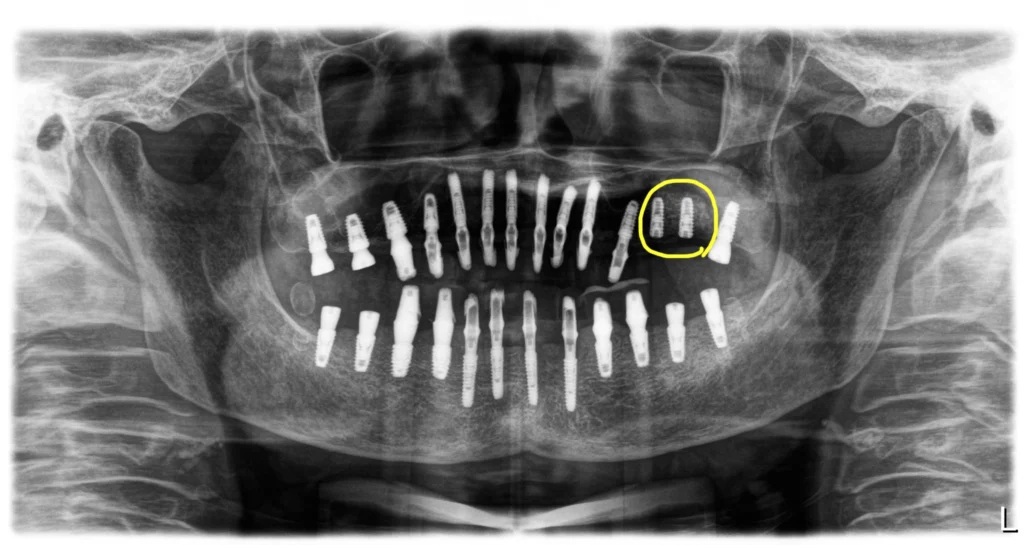

틀니를 하시려고 치아를 모두 뽑았고 잇몸은 모두 다 나은 상태로 내원하셨어요. 파노라마 엑스레이상으로 하악골은 양호한 편이었으나, 상악 구치부에는 상악동이 아래로 쳐져 있어 뼈가 부족한 상태였습니다.

그래서 전체임플란트로 치료를 결정하고 상악동 윈도우 방식의 뼈이식을 계획했어요.

우측에는 고정이 나와 상악동 뼈이식과 임플란트 식립을 동시에 할 수 있었지만 좌측에는 뼈가 무르고 상태가 좋지 않아 상악동 윈도우 뼈이식만 하고 제일 마지막 부위에 임플란트만 심어두었습니다.